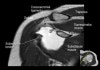

- Sagittal section

1) T1WI : Rotator cuff muscle size, fat infiltration, Biceps tendinosis

2) T2WI : Rotator cuff insertion, edema, Rotator cuff partial or full thickness tear, Bursa fluid collection, Acromial type ,Glenoid fossa, Superior, middle, inferior GHL

근육 안에 tendon이 들어있다

원외부에서 SST와 IST가 겹침